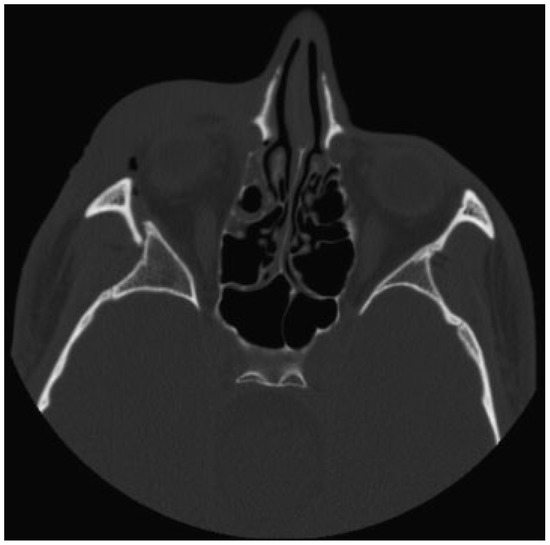

The authors defined simple LOWF as any fracture consisting of two boney pieces (Figure 1) and comminuted fractures as any fracture consisting of three or more pieces (Figure 2). Only patients who sustained fractures through primary trauma were included in this study. This excluded patients whose fractures were due to tumor resection or patients with a history of previous fractures of the lateral orbit. The senior investigator (W.S.) of this study identified the presence of all fractures, which were also confirmed upon review of the official radiology report.

Figure 2.

Comminuted lateral orbital wall fracture.